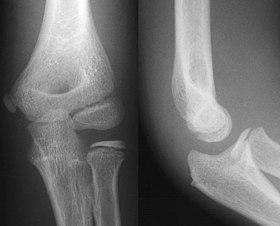

- 1.1 Examples of heterogeneous medical imaging modalities illustrating the diversity in data (X-ray, CT, and MRI).

- (a) X-ray of an arm11footnotemark: 1

Secondly, the heterogeneity of medical data, in terms of imaging modalities and tasks, adds another layer of complexity. Different modalities, such as X-rays, CT scans, and MRIs, each offer unique insights but also present distinct challenges, this is further underscored by the multitude of medical specializations in certain organs or body parts, see figure 1.1. These two factors cause the overall field to generate very distinct data, a brain CT image will have very little in common with an X-Ray of an arm. We believe this is one of the crucial reasons why self-supervised methods haven’t been as prevalent in the medical domain even if, in the natural imaging setting, these are key in obtaining state-of-the-art results. This characteristic also applies in the more general sense to the prospects of transfer learning and representation learning. For natural images, the use of models pre-trained on ImageNet as starting points to learning a new task is common and works very well due to the homogeneity of these images, all contain similar patterns and shapes. These properties aren’t present for medical images making the task, of learning good general representations that can be reused for any type of medical imaging modality, much harder. This motivated us to also look into developing ways to train a foundational model that can seamlessly adapt to this diversity and extract pertinent features across various modalities that can be reused for finetuning on downstream tasks. Our research introduces the Medformer architecture, a neural network structure adept at multitask learning and deep domain adaptation, specifically tailored for medical image analysis.